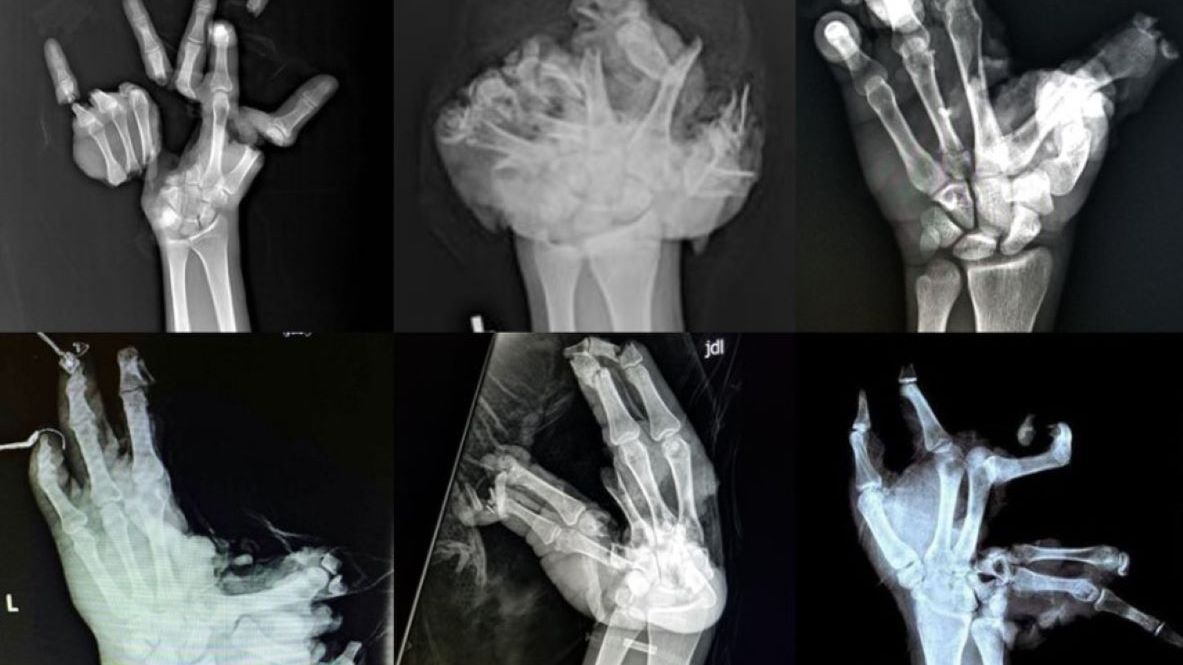

W poście na Facebooku ratownicy udostępnili zdjęcia rentgenowskie dłoni po "spotkaniu" z fajerwerkami i petardami. Na obrazach widnieją drastycznie połamane i porozrywane palce.